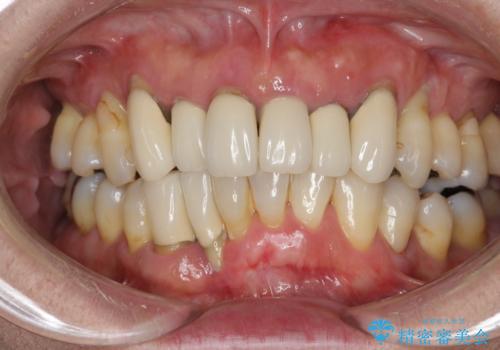

インプラントを用いた歯周病全顎治療

担当医 大元洋佑